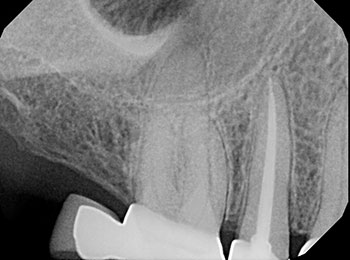

Root canal treatment is a procedure in which the nerve or pulp of the tooth is removed. Patients can need root canals for many different reasons. Is is most common when there is either inflammation or infection of the nerve of the tooth. Sometime a root canal is simply necessary due to lack of tooth structure to restore the tooth. During a root canal, the dentist will isolate the area and carefully clean, shape, disinfect, and fill the canals of the roots to seal the space. Most often we will recommend a crown to help strengthen the tooth and prevent it from fracturing.

Before root canal

After root canal